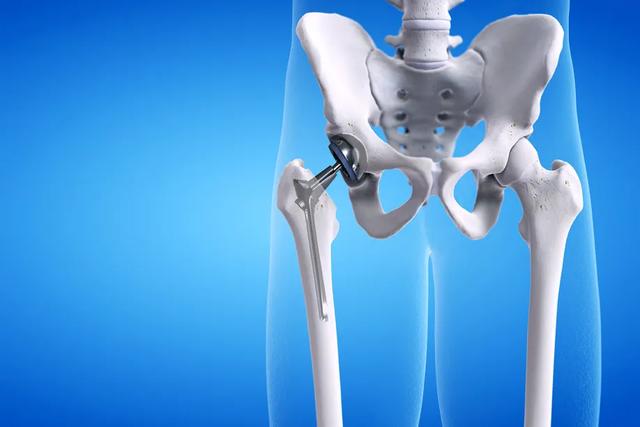

Il y a aussi le cas où certaines personnes n'ont pas les moyens d'agir.Patients opérés d'une prothèse de hancheDans le cas des patients plus âgés en particulier, nous devons utiliser du ciment osseux pour cimenter la prothèse à l'os, et parfois, lors de la mise en place de la prothèse, nous devons utiliser du ciment osseux.ciment osseuxLorsque la tension artérielle et le rythme cardiaque du patient sont anormaux, le chirurgien et l'anesthésiste se tiendront prêts à surveiller les signes vitaux du patient à tout moment avant d'insérer la prothèse et d'utiliser le ciment osseux, afin que les signes vitaux du patient soient surveillés à tout moment et que le patient soit réanimé rapidement en cas de problème, et le chirurgien expliquera également la possibilité de cette situation au patient ainsi qu'à ses proches avant de procéder à l'opération de remplacement de l'articulation de la hanche.

- fig. dépenser de l'argentLe tissu osseux est richement hématogène, en particulier dans les sections osseuses, les cavités de la moelle osseuse ou le canal rachidien, et les saignements sont généralement importants et difficiles à contrôler. Certaines des procédures les plus invasives, telles queLes saignements seront plus élevés en cas d'arthroplastie totale de la hanche, de chirurgie rachidienne et de chirurgie pelvienne.. Si l'hémorragie peropératoire est importante, un choc hémorragique peut se produire. Bien qu'une transfusion sanguine peropératoire soit possible, une perte de sang importante peut toujours être physiquement intolérable pour les personnes âgées dont la fonction cardio-pulmonaire est faible.